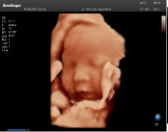

容積探頭是在二維圖像的基礎(chǔ)上,將連續(xù)采集的空間分布位置,經(jīng)過計(jì)算機(jī)重建算法,從而獲得完整的空間形態(tài)。

適用于:胎兒面部、脊柱和肢體等。

優(yōu)勢特點(diǎn):快速獲取、掃查連續(xù)均勻、解剖結(jié)構(gòu)顯示為容積數(shù)據(jù)、準(zhǔn)確進(jìn)行容積測量。